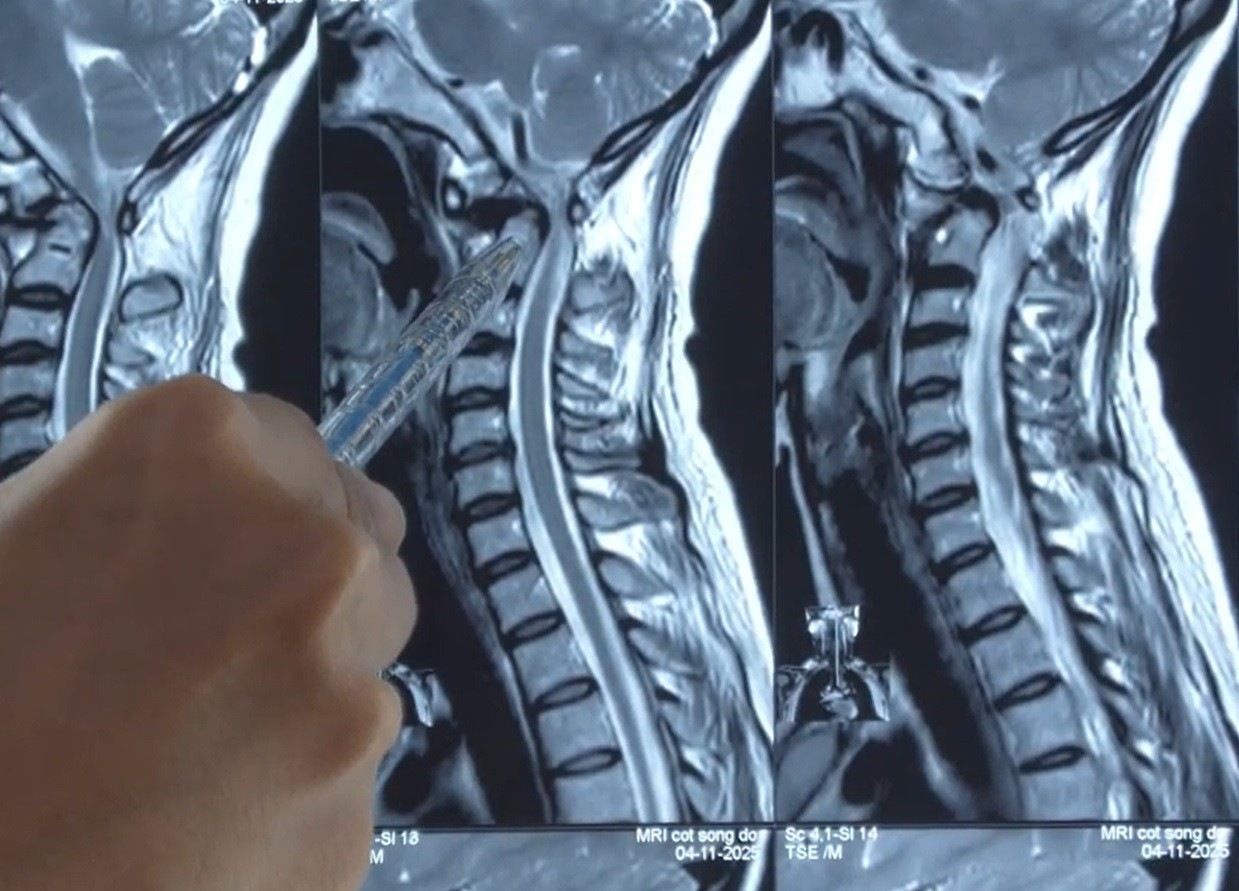

Trong chuyến công tác tại Hàn Quốc, chị bất ngờ ngất giữa sân bay và được đưa đi cấp cứu. Kết quả MRI tại nước bạn cho thấy cột sống cổ bệnh nhân bị trượt tại vị trí C1–C2, gây hẹp nặng ống tủy. Tại đây, bác sĩ khuyến cáo chị phải phẫu thuật càng sớm càng tốt để tránh nguy cơ liệt tứ chi.

Trở về nước, người bệnh đã đến Bệnh viện Đa khoa Xuyên Á TP.HCM điều trị. ThS.BS Trần Vũ Hoàng Dương, Trưởng khoa Sọ não Cột sống 2 của bệnh viện cho biết, bệnh nhân bị trượt đốt sống C1–C2 gây mất vững cột sống cổ và chèn ép tủy nặng. Đây chính là nguyên nhân khiến chị tê dị cảm tứ chi, yếu nửa người bên trái và liên tục ngất xỉu. Chỉ cần một cú ngã nhẹ hoặc xoay cổ sai tư thế, bệnh nhân có thể đối diện nguy cơ liệt tứ chi.

Theo BS Hoàng Dương, cấu trúc bình thường của cột sống cho phép mỏm nha C2 liên kết chặt với thân đốt sống. Nhưng ở bệnh nhân Y. mỏm nha rời khỏi thân, kết hợp với trượt đốt sống đã ép chặt vào tủy cổ – vị trí cực kỳ nguy hiểm. Tình trạng này khiến các dây thần kinh vận động bị đe dọa nghiêm trọng, gây tê yếu tứ chi và suy giảm thị lực.

Vị trí đốt sống cổ của người bệnh bị trượt chèn ép tủy sống gây nguy cơ liệt tứ chi.

“Không phẫu thuật, bệnh sẽ tiến triển đến liệt tứ chi, thậm chí liệt cơ hô hấp dẫn đến suy hô hấp cấp. Sau hội chẩn, ê kíp đã quyết định can thiệp phẫu thuật cố định đốt sống C1–C2 và giải áp tủy. Đây là một trong những kỹ thuật khó nhất của ngoại thần kinh cột sống. Khu vực C1–C2 rất nhỏ, nằm cạnh tủy cổ, động mạch đốt sống và nhiều cấu trúc thần kinh quan trọng. Chỉ một sai lệch vài milimet cũng có thể gây biến chứng nguy hiểm” - bác sĩ Hoàng Dương cho biết.